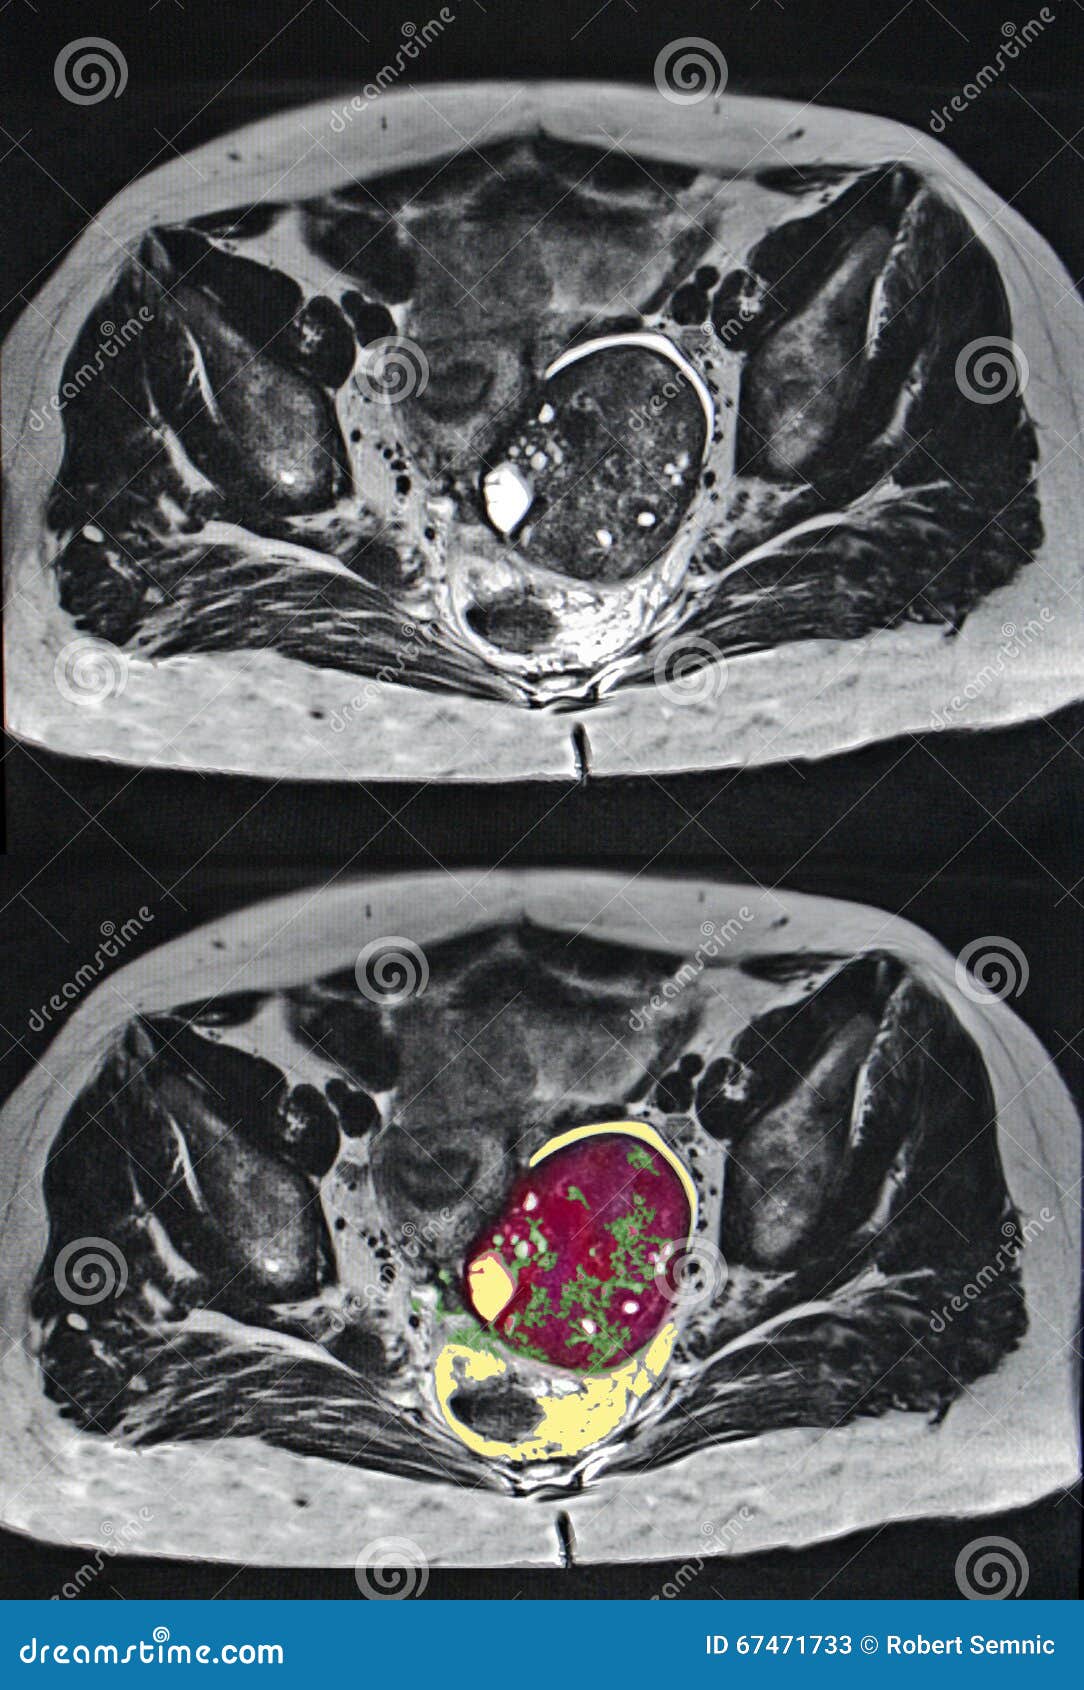

Примеры фото МРТ малого таза у женщин

Ниже представлены примеры фотографий МРТ малого таза у женщин, позволяющие увидеть, как выглядят снимки и какие изменения могут быть обнаружены специалистами.